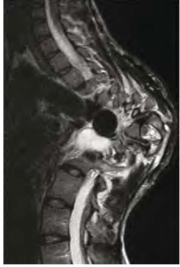

| 06:26, 3 באוגוסט 2014 | נוירוגנית5.png (קובץ) |  |

243 קילו־בייטים | Motyk | 1 | |